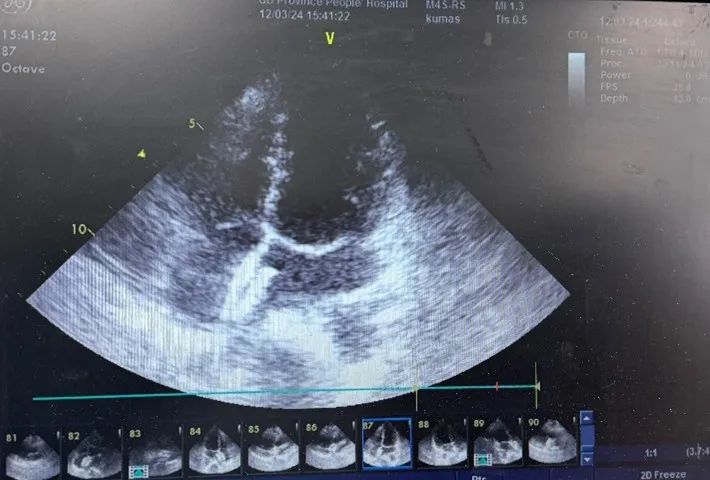

术前经手术团队充分评估、讨论,结合患者及家属意愿,考虑采用佰仁医疗PFO封堵器进行治疗。手术经超声引导,穿刺右股静脉建立手术路径,超声评估测量后,予患者植入25-25#佰仁思®PFO封堵器一枚,手术过程顺利,封堵器释放位置良好、贴壁良好,术后超声未见残余分流。患者次日即出院,截至目前无头痛、头晕复发。

图片

封堵术后超声